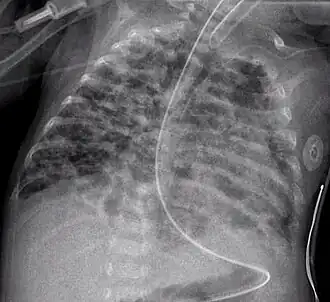

Radiographie thoracique d'un enfant atteint de dysplasie bronchopulmonaire.